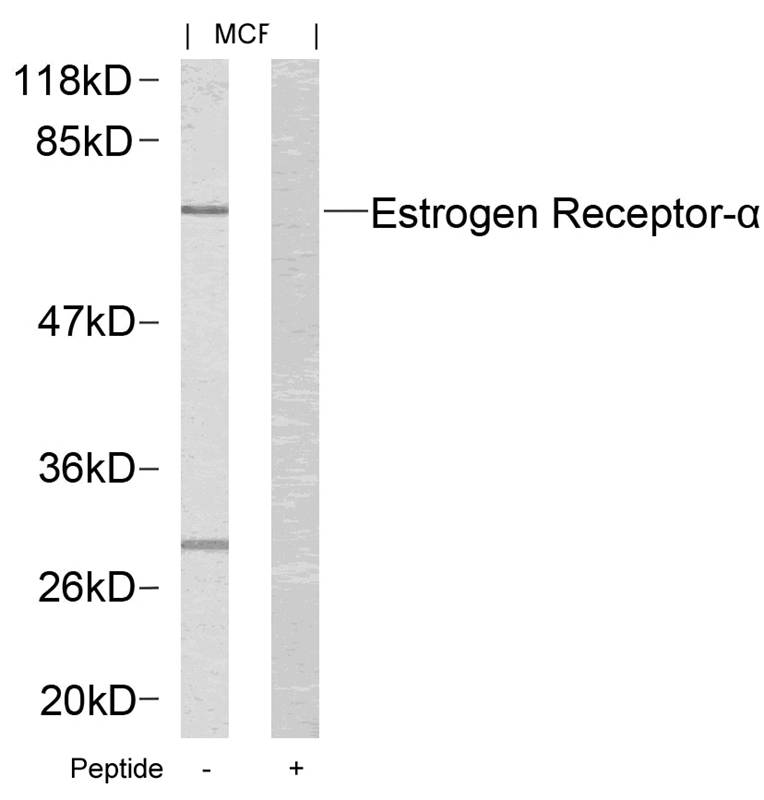

分类: 科研抗体货号: P41296别名: ER; ESR; ESR1; ESTR; ESTRA应用: WB,IHC,IF反应种属: Human